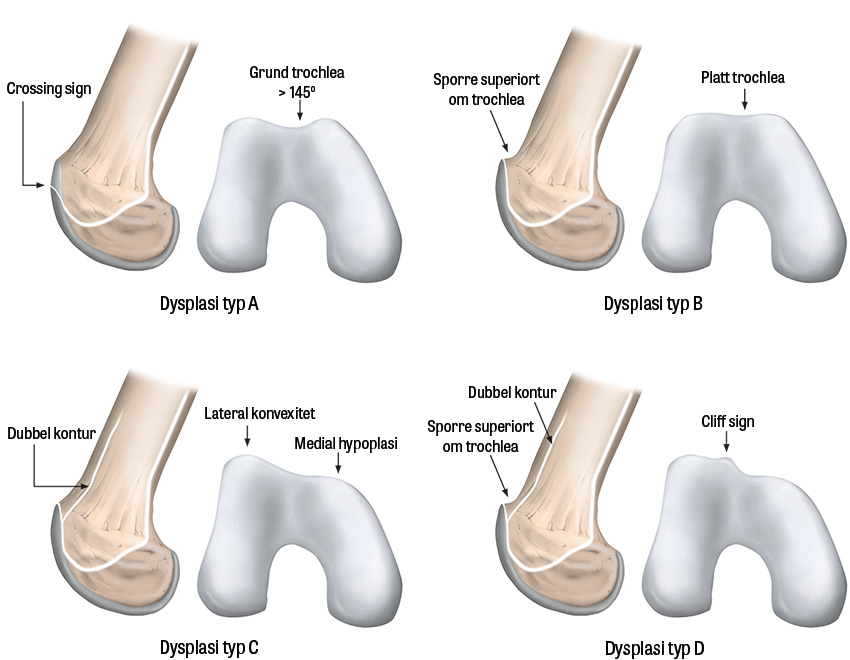

Trochleadysplasi. Utvecklingsrubbning med gradvis stigande utfyllning av trochleas golv, vilket resulterar i en utplaning av trochleas fåra som till slut blir platt eller konvex, ledande till sämre stabilisering av patella.

Slätröntgen av knät bör omfatta tre projektioner: anteroposterior, lateral med knät i 30 graders flexion samt femoropatellär vy (Merchants vy) [11]. Subluxation, patellar tilt och trochleadysplasi värderas med Merchants vy, medan patella alta bedöms lättast med den laterala vyn.